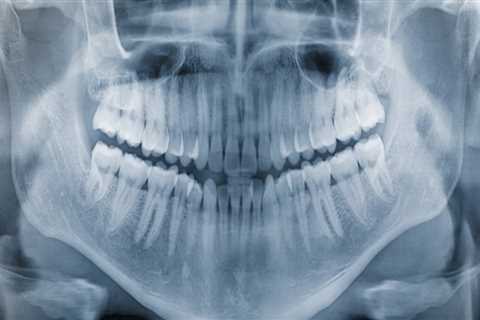

How Dental X-Rays Help Detect Problems Before They Become Serious

A bright, healthy smile doesn’t just depend on regular brushing, flossing, and checkups—it also..

Discover the Essential Role of Dental X-Rays in Dentistry Discover the Essential Role of Dental X-Rays in Dentistry

Learn how dental X-rays aid in accurate diagnosis and personalized care at Maidu Dental in Auburn,..

Why Dental X-Rays Are Essential For Craniomandibular Dysfunction Treatment In Basel Why Dental X-Rays Are Essential For Craniomandibular Dysfunction Treatment In Basel

Understanding the complete picture of craniomandibular dysfunction begins with the proper..